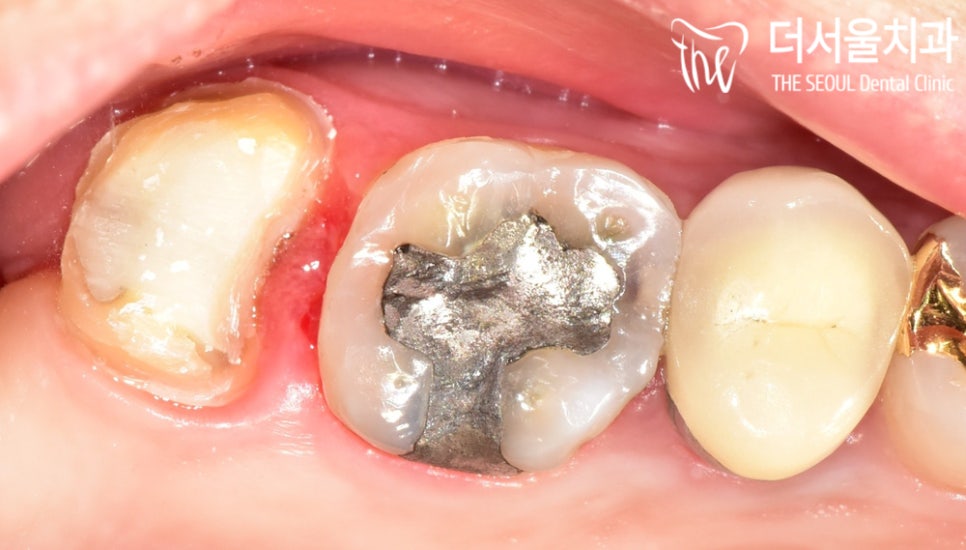

육안 관찰 결과,

통증 이 생긴 곳에 아말감으로 추정되는 것이

씌워져 있는 것을 확인할 수 있었습니다.

음.. 일부분이 깨져있었는데요.

별로 상황이 좋지만은 않았습니다.

약 7년 가까이 아말감을 사용하고 있었는데요.

정말 잘 판단하신 겁니다.